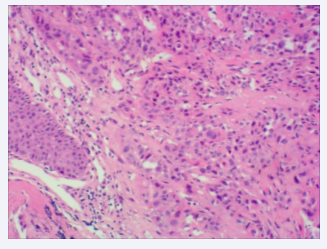

Biopsies were obtained during bronchoscopy at the opening of the middle and lower lobes, and bronchoalveolar lavage was performed on the lower lobe of the right lung. The culture and cytology of the bronchoalveolar lavage fluid were negative. A set of biopsy specimens, stained with hematoxylin and eosin (HE), indicated SCC in the right middle lobe and an inflammatory response in the lower lobe of the right lung (Figures 3,4).

HE staining of the tissue showing inframammary response  (×100).

Figure 4: HE staining of the tissue showing inframammary response (×100).